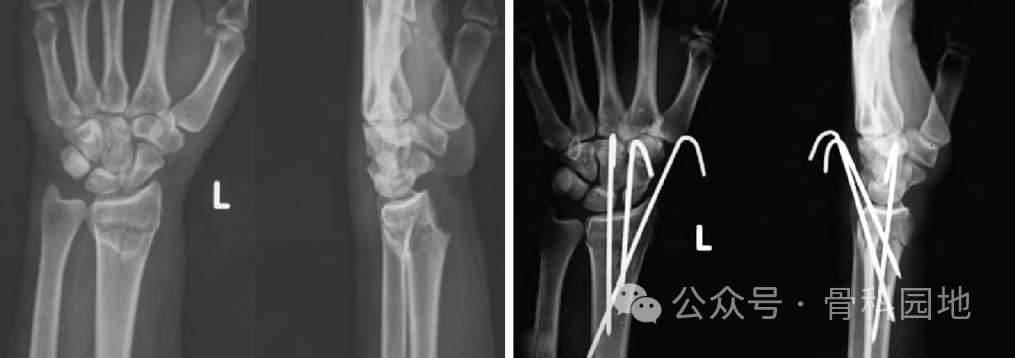

首先进行骨折闭合复位,牵引时须缓慢而持续,通过掌屈和尺偏来矫正背侧和桡侧移位。复位后,将手放在卷起的布单上,保持掌屈和尺偏(下图a,b),并用至少三根经皮克氏针固定。

第一枚克氏针在 Lister 结节进针,以 45°倾斜,瞄准桡骨长轴上近端骨块的掌侧皮层。如果进针点位于Lister结节的尺侧,可能会损伤拇伸肌腱。

第二枚克氏针自桡骨茎突远端 0.5 cm 处进针,克氏针与桡骨轴成 60°角,穿透骨折近端尺侧皮质。

第三枚克氏针在距腕关节线远端0.5 cm处,固定月骨窝骨块,位于第四和第五伸肌室之间。克氏针以 45 °角固定到桡骨的掌侧,如下图a、b 所示。

使用经典经皮克氏针固定桡骨远端骨折,如下图a-e 。